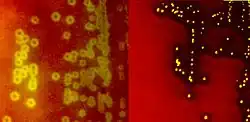

Species of streptococci are classified based on their hemolytic properties.[10] Alpha-hemolytic species cause oxidization of iron in hemoglobin molecules within red blood cells, giving it a greenish color on blood agar. Beta-hemolytic species cause complete rupture of red blood cells. On blood agar, this appears as wide areas clear of blood cells surrounding bacterial colonies. Gamma-hemolytic species cause no hemolysis.[11]

When alpha-hemolysis (α-hemolysis) is present, a blood based agar under the colony will appear dark and greenish due to the conversion of hemoglobin to green biliverdin. Streptococcus pneumoniae and a group of oral streptococci (Streptococcus viridans or viridans streptococci) display alpha-hemolysis. Alpha-hemolysis is also termed incomplete hemolysis or partial hemolysis because the cell membranes of the red blood cells are left intact. This is also sometimes called green hemolysis because of the color change in the agar.

Beta-hemolysis (β-hemolysis), sometimes called complete hemolysis, is a complete lysis of red cells in the media around and under the colonies: the area appears lightened (yellow) and transparent. Streptolysin, an exotoxin, is the enzyme produced by the bacteria which causes the complete lysis of red blood cells. There are two types of streptolysin: Streptolysin O (SLO) and streptolysin S (SLS). Streptolysin O is an oxygen-sensitive cytotoxin, secreted by most group A Streptococcus (GAS), and interacts with cholesterol in the membrane of eukaryotic cells (mainly red and white blood cells, macrophages, and platelets), and usually results in beta-hemolysis under the surface of blood agar. Streptolysin S is an oxygen-stable cytotoxin also produced by most GAS strains which results in clearing on the surface of blood agar. SLS affects immune cells, including polymorphonuclear leukocytes and lymphocytes, and is thought to prevent the host immune system from clearing infection. Streptococcus pyogenes, or GAS, displays beta hemolysis.